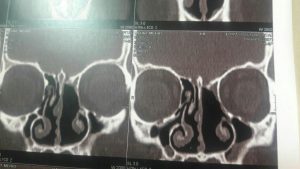

2. سی تی اسکن

تشخیص به وسیله این روش تصویربرداری دقیق تر از سایر روشها می باشد زیرا میزان درگیری استخوان از این طریق نشان می دهد. همچنین برای تشخیص تومور در اطراف مغز از این روش استفاده می شود.

این عکس ها متعلق به خانمی ۵۲ ساله با سابقه گرفتگی بینی از چند سال قبل و نیز سابقه جراحی پولیپ در ۱۰ سال گذشته می باشد در بررسی بالینی نکته دیگری جز توده ای به ظاهر پولیپ مانند در بینی نبود. محل کلی تومور با خط مشکی مشخص شده است

که در تصویر برداری با سی تی اسکن بینی و سینوس نمای موجود شک به این نوع پاپیلوم را برمی انگیخت که طی عمل جراحی اندوسکوپیک و کمک مداوم سر جراحی از همکاران پاتولوژیست وجود این توده ثابت گردیید. و متاسفانه محل پیدایش و منشا اولیه آن در قاعده جمجمه و در محل نازک ترین قسمت استخوان بین بینی و سینوس ها و مغز به طور عملی محرز گردید و این نایحه به طور کامل با کمک ابزارهای خاص تراشیده شده و عمل با اطمینان از برداشت کامل بدون آسیب و صدمه به عناصر حیاتی نظیر مز خاتمه پیدا کرد.